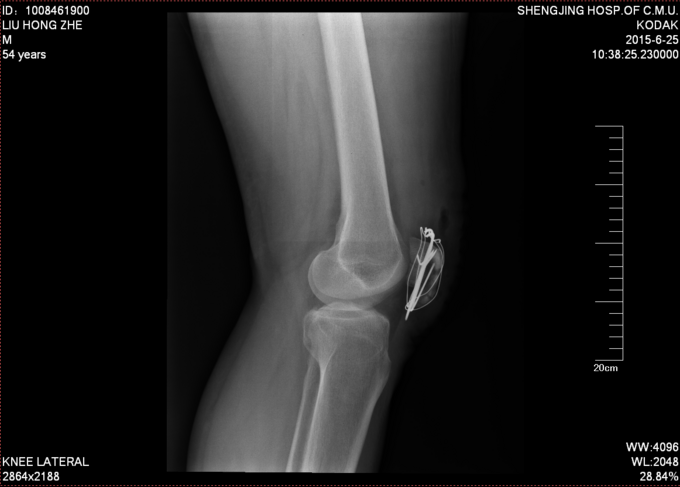

患者自诉于2015年5月17日晚21点多在外不慎摔伤,致左膝部疼痛肿胀活动受限,当时无意识不清,急诊送当地医院(铁岭市中心医院),行左膝关节DR及三维CT:左髌骨骨折。今为进一步治疗急于我院中国医科大学附属盛京医院,行X线片检查示:左髌骨骨折,急诊以“左髌骨骨折”为诊断收住入院。

专科查体:患者轮椅入病房,左膝部肿胀明显,疼痛,压痛(+),活动受限,骨擦音,骨擦感(+), 患肢足趾活动可,足背动脉可触及。

诊断:左髌骨骨折 患者入院后左膝部抬高,冷疗,消肿等对症治疗后,约一周后行左髌骨骨折切开复位张力带内固定术。